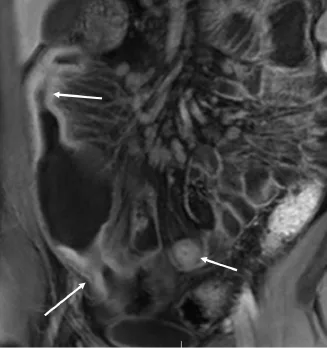

Elle permet tout d’abord de réaliser une cartographie de l’atteinte : atteinte courte et limitée à la dernière anse ou atteinte multifocale de l’ensemble du jéjunum et de l’iléon par exemple (Fig. 2).

Figure 2. Patient de 32 ans ayant une maladie de Crohn connue. Séquence d’entéro-IRM en pondération T1 après injection de gadolinium dans le plan coronal montrant une atteinte multifocale de l’iléon avec sténoses et dilatations présténotiques entre les atteintes successives